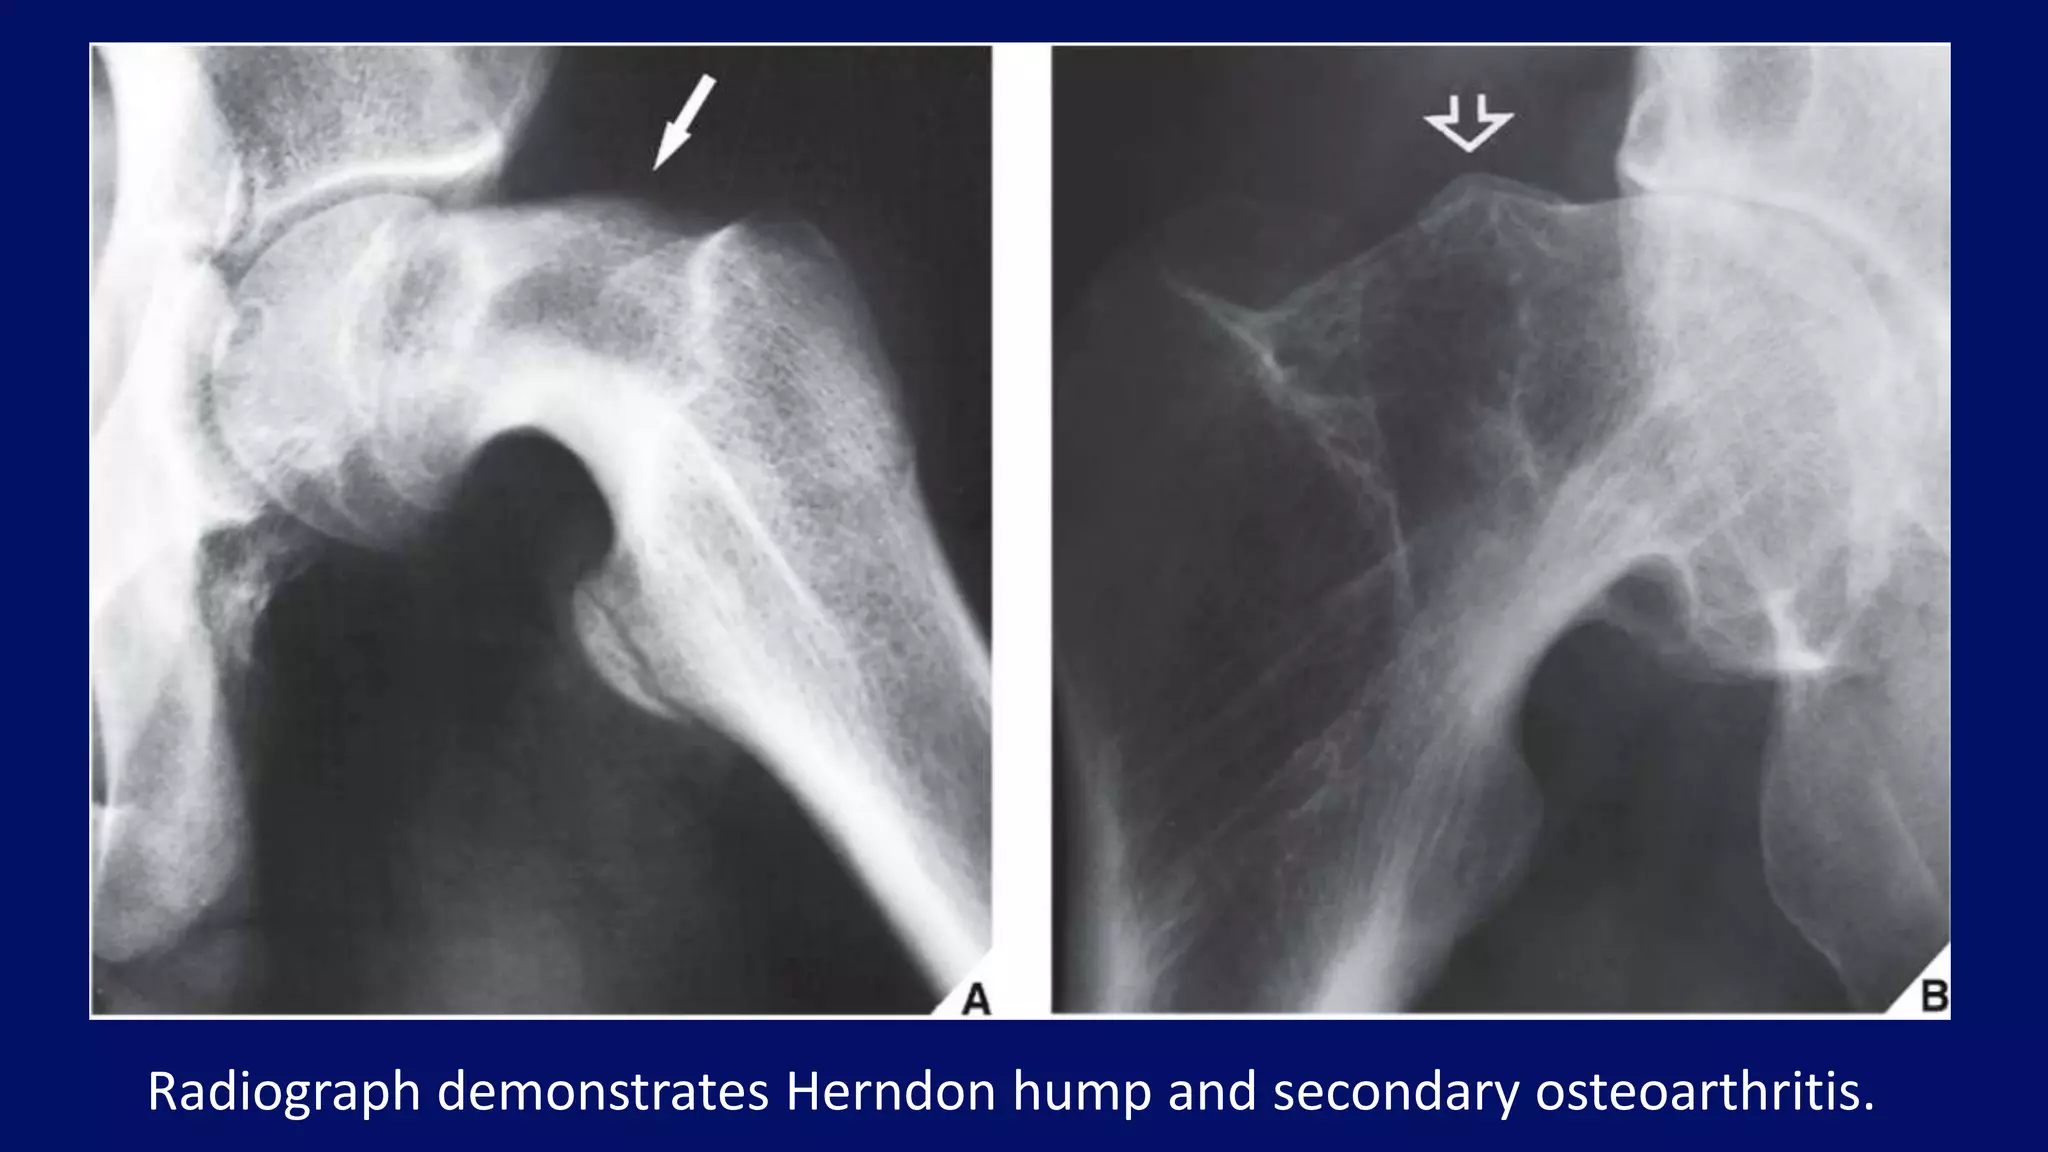

• Herndon hump

Slipped capital femoral epiphysis

Radiographic features:

Radiograph demonstrates Herndon hump and secondary osteoarthritis.

• #73 Chronic stages of this disorder exhibit reactive bone formation along the superolateral aspect of the femoral neck, along with remodeling; this creates a protuberance and broadening of the femoral neck, which gives it a “pistol-grip” appearance known as a Herndon hump